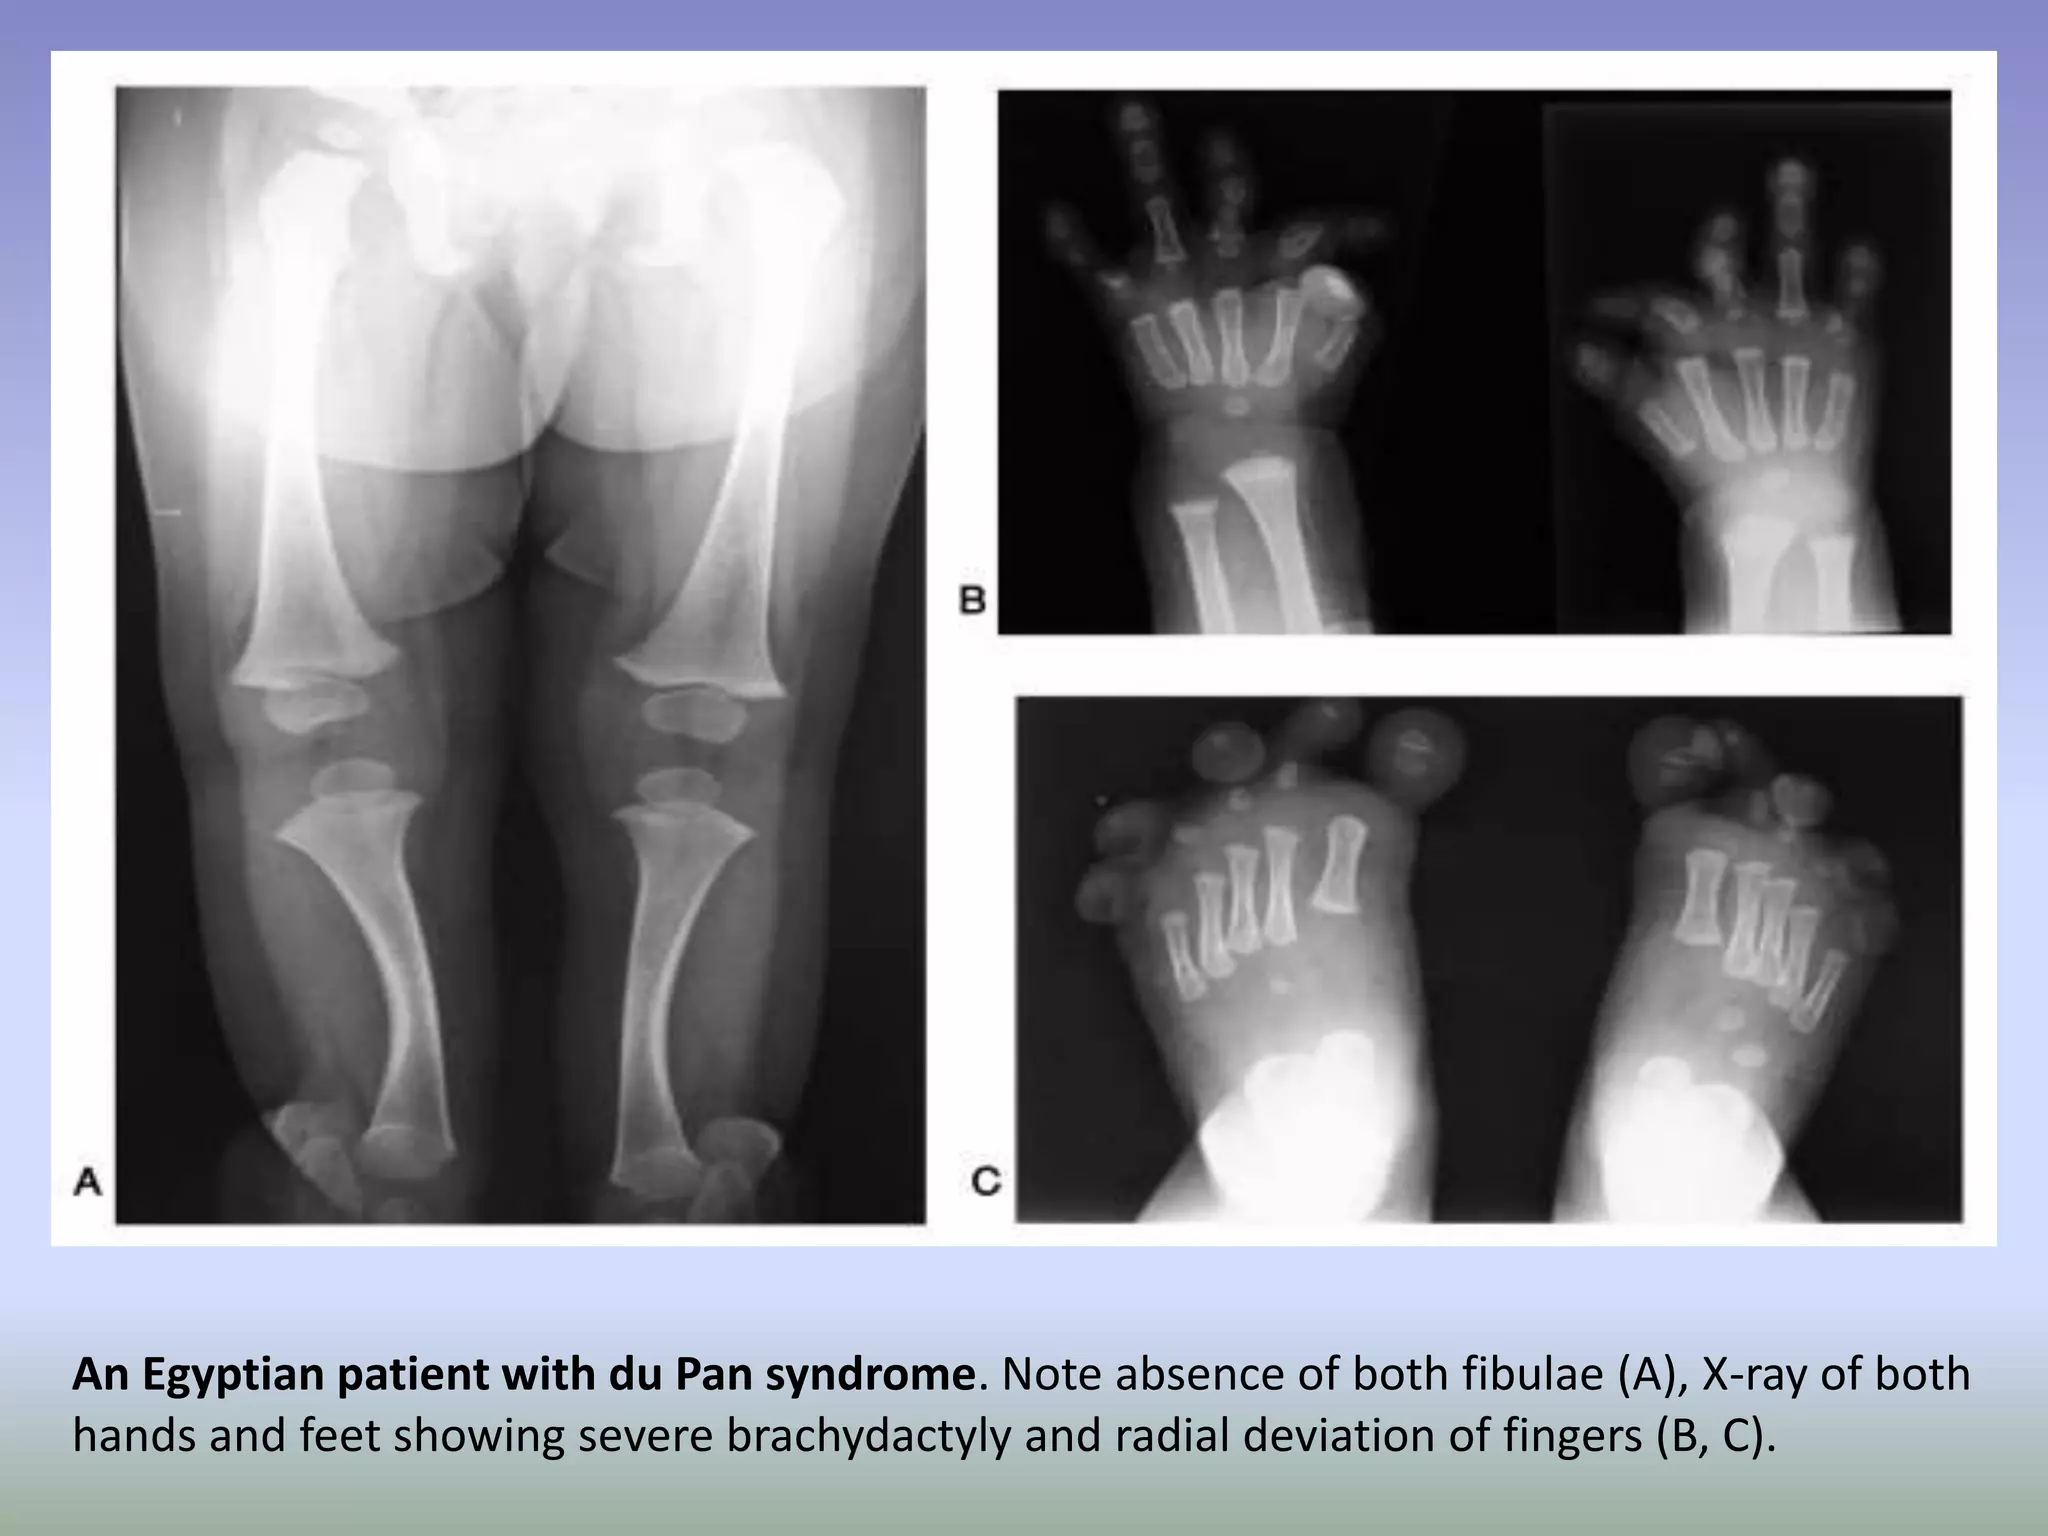

Du Pan Syndrome causes skeletal abnormalities and short stature.

In this disease, the GDF5 gene responsible for regulating cell growth

and differentiation is defective. Individuals with Du Pan Syndrome

have typical trunk size but shortened limbs. Fibulae, the smaller of

the two long bones that join the knee to the ankle, are rudimentary

or absent. Knees and ankles are contorted. In addition, fingers are

stumpy and bent in atypical directions. Thumbs and toes are small,

button-like, and non-functional. Affected individuals are of typical

intelligence.

Du Pan syndrome is very rare, with less than 30 cases reported.

Therefore, incidence of this condition is thought to be less than 1 in

1,000,000. Almost all the affected individuals reported have been

from Middle Eastern countries.

Prognosis is generally favorable. Skeletal symptoms may be

progressive with age and growth. However, affected individuals are

of typical intelligence and do not have a shortened lifespan.

An Egyptian patient with du Pan syndrome. Note absence of both fibulae (A), X-ray of both

hands and feet showing severe brachydactyly and radial deviation of fingers (B, C).

Du Pan Syndromecauses skeletal abnormalities and short stature. In this disease, the GDF5 gene responsible for regulating cell growth and differentiation is defective. Individuals with Du Pan Syndrome have typical trunk size but shortened limbs. Fibulae, the smaller of the two long bones that join the knee to the ankle, are rudimentary or absent. Knees and ankles are contorted. In addition, fingers are stumpy and bent in atypical directions. Thumbs and toes are small, button-like, and non-functional. Affected individuals are of typical intelligence. Du Pan syndrome is very rare, with less than 30 cases reported. Therefore, incidence of this condition is thought to be less than 1 in 1,000,000. Almost all the affected individuals reported have been from Middle Eastern countries. Prognosis is generally favorable. Skeletal symptoms may be progressive with age and growth. However, affected individuals are of typical intelligence and do not have a shortened lifespan.

An Egyptian patientwith du Pan syndrome. Note absence of both fibulae (A), X-ray of both hands and feet showing severe brachydactyly and radial deviation of fingers (B, C).